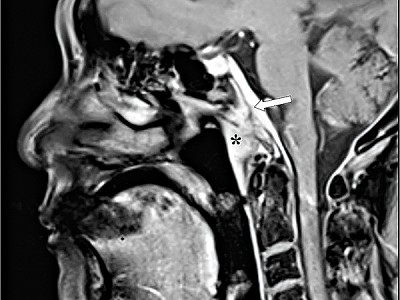

圖2:陳女士治療前的檢查圖片,發現

在左鼻咽處有5厘米大的腫瘤

張文龍醫生參考有關資料後,利用標靶藥物配合化療治療晚期的鼻咽癌患者。70歲陳女士,在去年4月突然感到頭痛,睡覺時的情況更為嚴重,而且服止痛藥亦未能止痛,檢查後發現在其左鼻咽處有一顆5厘米大的腫瘤,證實為第4期的鼻咽癌,而該腫瘤逼近視覺神經及腦部,亦已引致左眼下裂,陳女士本身右眼早已失明。